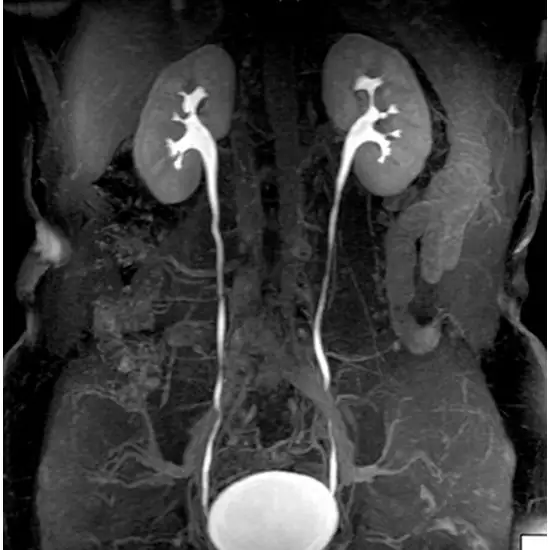

This imaging test evaluates the exact condition of the kidney, ureter and bladder for detecting stones and other kinds of disorders in urinary tract.

MRI Kidney, Ureter and Bladder (KUB) are properly diagnosed with the effective use of a highly advanced scanner to detect kidney stones and diagnose the urinary tract for any kind of disorder.

MRI KUB with contrast is a Magnetic Resonance Imaging non-invasive medical diagnostic tool that uses contrast for the detection of abnormalities in the kidney, urethra and bladder. MRI KUB with contrast is used to show urinary tract infection, kidney stones, and renal perfusion etc.